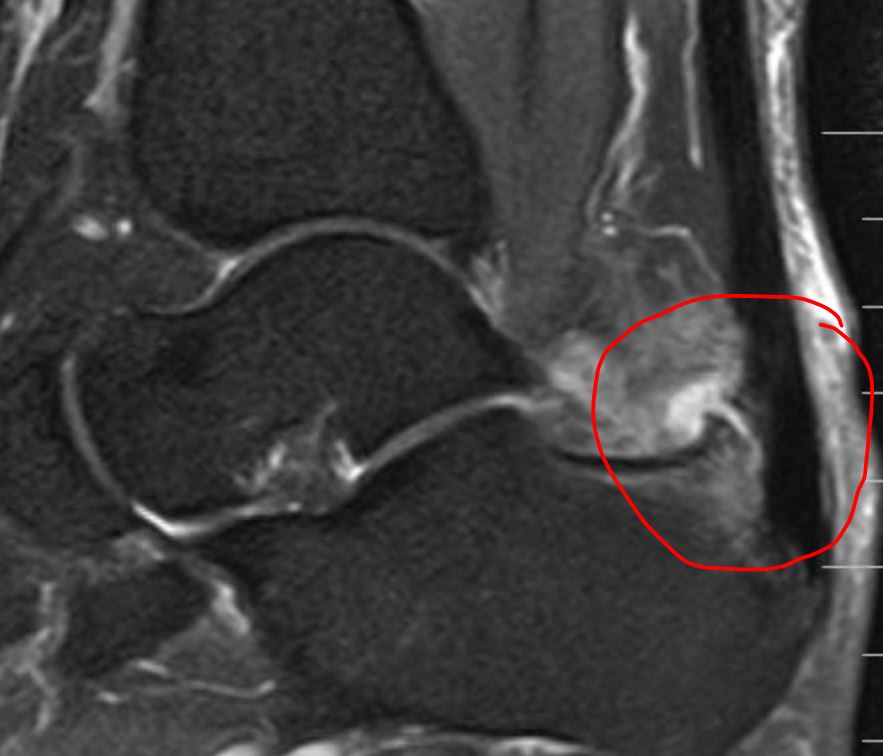

跟腱钙化是肌腱钙盐沉积导致,钙化的跟腱在X光下会表现为高亮度,和骨骼的亮度是相接近的。如果患者长时间进行剧烈运动,或进行繁重体力劳动等,都容易反复牵拉跟腱部位的胶原纤维,从而引起局部组织韧带损伤,出现跟腱钙化。在出现跟腱钙化后,可能表现为不能长时间站立、走路疼痛、跟腱水肿等症状

跟腱止点腱炎指在跟腱止点(跟腱与跟骨结合部,腱骨结合区域)处的足后跟疼痛。开始在活动多后感到疼痛,之后可转为持续性疼痛。检查可见跟腱止点部外观正常或增大,局部压痛。

如果症状得不到缓解或加重,也可以选择在正规医院通过手术切除跟腱钙化部位,从而缓解此症状。手术中使用缝合锚重建跟腱止点,建议使用双排锚钉构建来增加强度。术后恢复性锻炼至少需要9个月。